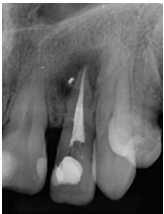

Para la obturación se utilizó la técnica de condensación lateral y se usó un cemento bioactivo BioRoot RCS.

Figura 2: Radiografía final del órgano dentario 1.2 Tratamiento endodóntico finalizado y obturación completa. Fecha: 15/08/2022

Fuente: Dra. Karina Tito, 2022